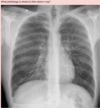

Your patient presented to ED with a four-day history of chest pain, fever, and malaise. After a thorough history and examination, you order a blood culture, CRP, FBC, LFTs, measure his BGLs and SpO2, and send him for a CXR.

Upon examination of his chest x-ray, what pathology is likely?

B ) Bronchopneumonia